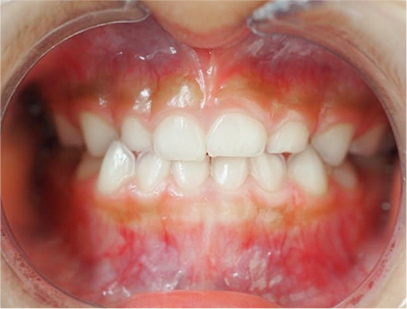

前歯部の開咬とデコボコ

前歯部が咬んでいないことを主訴として来院されました。精査、診断の結果「前歯部にデコボコを伴う開咬」と診断されました。

下の歯の裏側に舌が出ないように矯正装置を取り付け、そして上の歯には取り外しのできる矯正装置を装着して、側方に拡大を行います。

取り外しのできる矯正装置、舌が出せなくなる矯正装置(フェンス)

• 正面